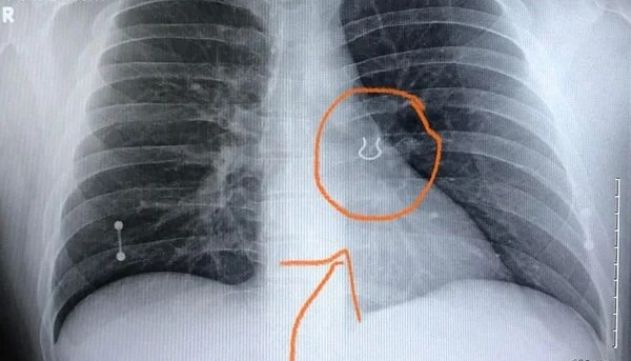

Em um relato feito nas redes sociais, o jardineiro Joey Lykins, 35 anos, conta uma situação inusitada que viveu no último mês. O americano foi socorrido após sofrer uma crise de tosse severa seguida de falta de ar, em um quadro semelhante ao de uma pneumonia. Ao chegar ao pronto socorro, descobriu que os sintomas eram provocados, na realidade, por um piercing alojado em seu pulmão há cinco anos.

O paciente contou aos médicos que provavelmente inalou o piercing usado no septo enquanto dormia. Lykins lembra de ter sentido falta da joia ao acordar em uma manhã de 2017. Ele revirou o quarto à procura do item, mas deu o piercing como perdido.

Com as imagens do raio-x, os médicos suspeitaram que a joia se moveu ligeiramente para dentro do pulmão nos últimos anos, provocando só agora a sensação de bloqueio das vias aéreas e tosse aguda. O objeto foi retirado com uma broncoscopia, procedimento feito com um tubo que passa pela garganta normalmente usado para fazer o diagnóstico de infecções ou remover objetos dos pulmões.